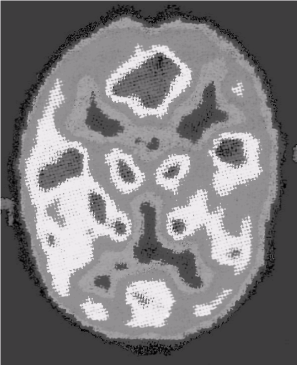

В XX веке в физике были совершены открытия и изобретения, касающиеся информации, новых методов познания внешнего мира, содержания сигналов, а также средств их доставки и связи. Из них в раздел «физика информации» можно сгруппировать открытия, получившие признание Нобелевского комитета: рентгенографии (К. Рентген, 1901); влияния магнетизма на процессы излучения (Х.Лоренс, П. Зееман, 1902); радиоактивности (П. Кюри, М. Склодовская-Кюри, 1903); электролитной диссоциации* (С.Аррениус, 1903); катодных лучей (Ф.Ленард, 1905); прецизионных оптических инструментов (Ф. Майкельсон, 1907); цветной фотографической репродукции (Г.Липман, 1908); беспроволочного телеграфа (радио) (Г.Маркони и Ф.Браун, 1909) (ранее — А.Попов); эффекта Доплера (И. Штарк, 1919); фотоэлектрического эффекта (А. Эйнштейн, 1922; Э.Милликен, 1923); строения атомов и испускаемого ими излучения (Н.Бор, 1922); электрокардиографии** (В. Эйнтховен, 1924); усовершенствования фотографии ядерных процессов и открытие мезонов (С. Пауэлл, 1950); измерения ядерного магнетизма (Ф. Блох, Э. Парселл, 1952); распределительной хроматографии* (А. Мартин, Р.Синг, 1952); фазоконтраст-ного микроскопа (Ф. Цернике, 1953); полупроводников и транзисторного эффекта (У. Шокли, Д. Бардин, у. Браттейн, 1956); полярографического анализа* (Я. Гейровский, 1959); метода датирования углеродом-14* (У.Либ-би, 1960); оптических методов исследования колебаний атомов в области радиочастот (А.Кастлер, 1966); процессов генерации энергии звезд (Х.Бете, 1967); голографии (Д.Габор, 1971); сверхпроводимости (Д. Бар дин, Л. Купер, Д.Шриффер, 1972); радиоастрономических (М.Райл, Э.Хьюиш, 1974); радиоиммунологических** (Р.Ялоу, 1977); томографических методов исследований** (А.Кормак, Г.Хаунсфилд, 1979); электронной микроскопии кристаллов и структур нуклеопротеиновых комплексов* (А. Клуг, 1982); электронной оптики, сканирующего туннельного микроскопа (Э. Руской,